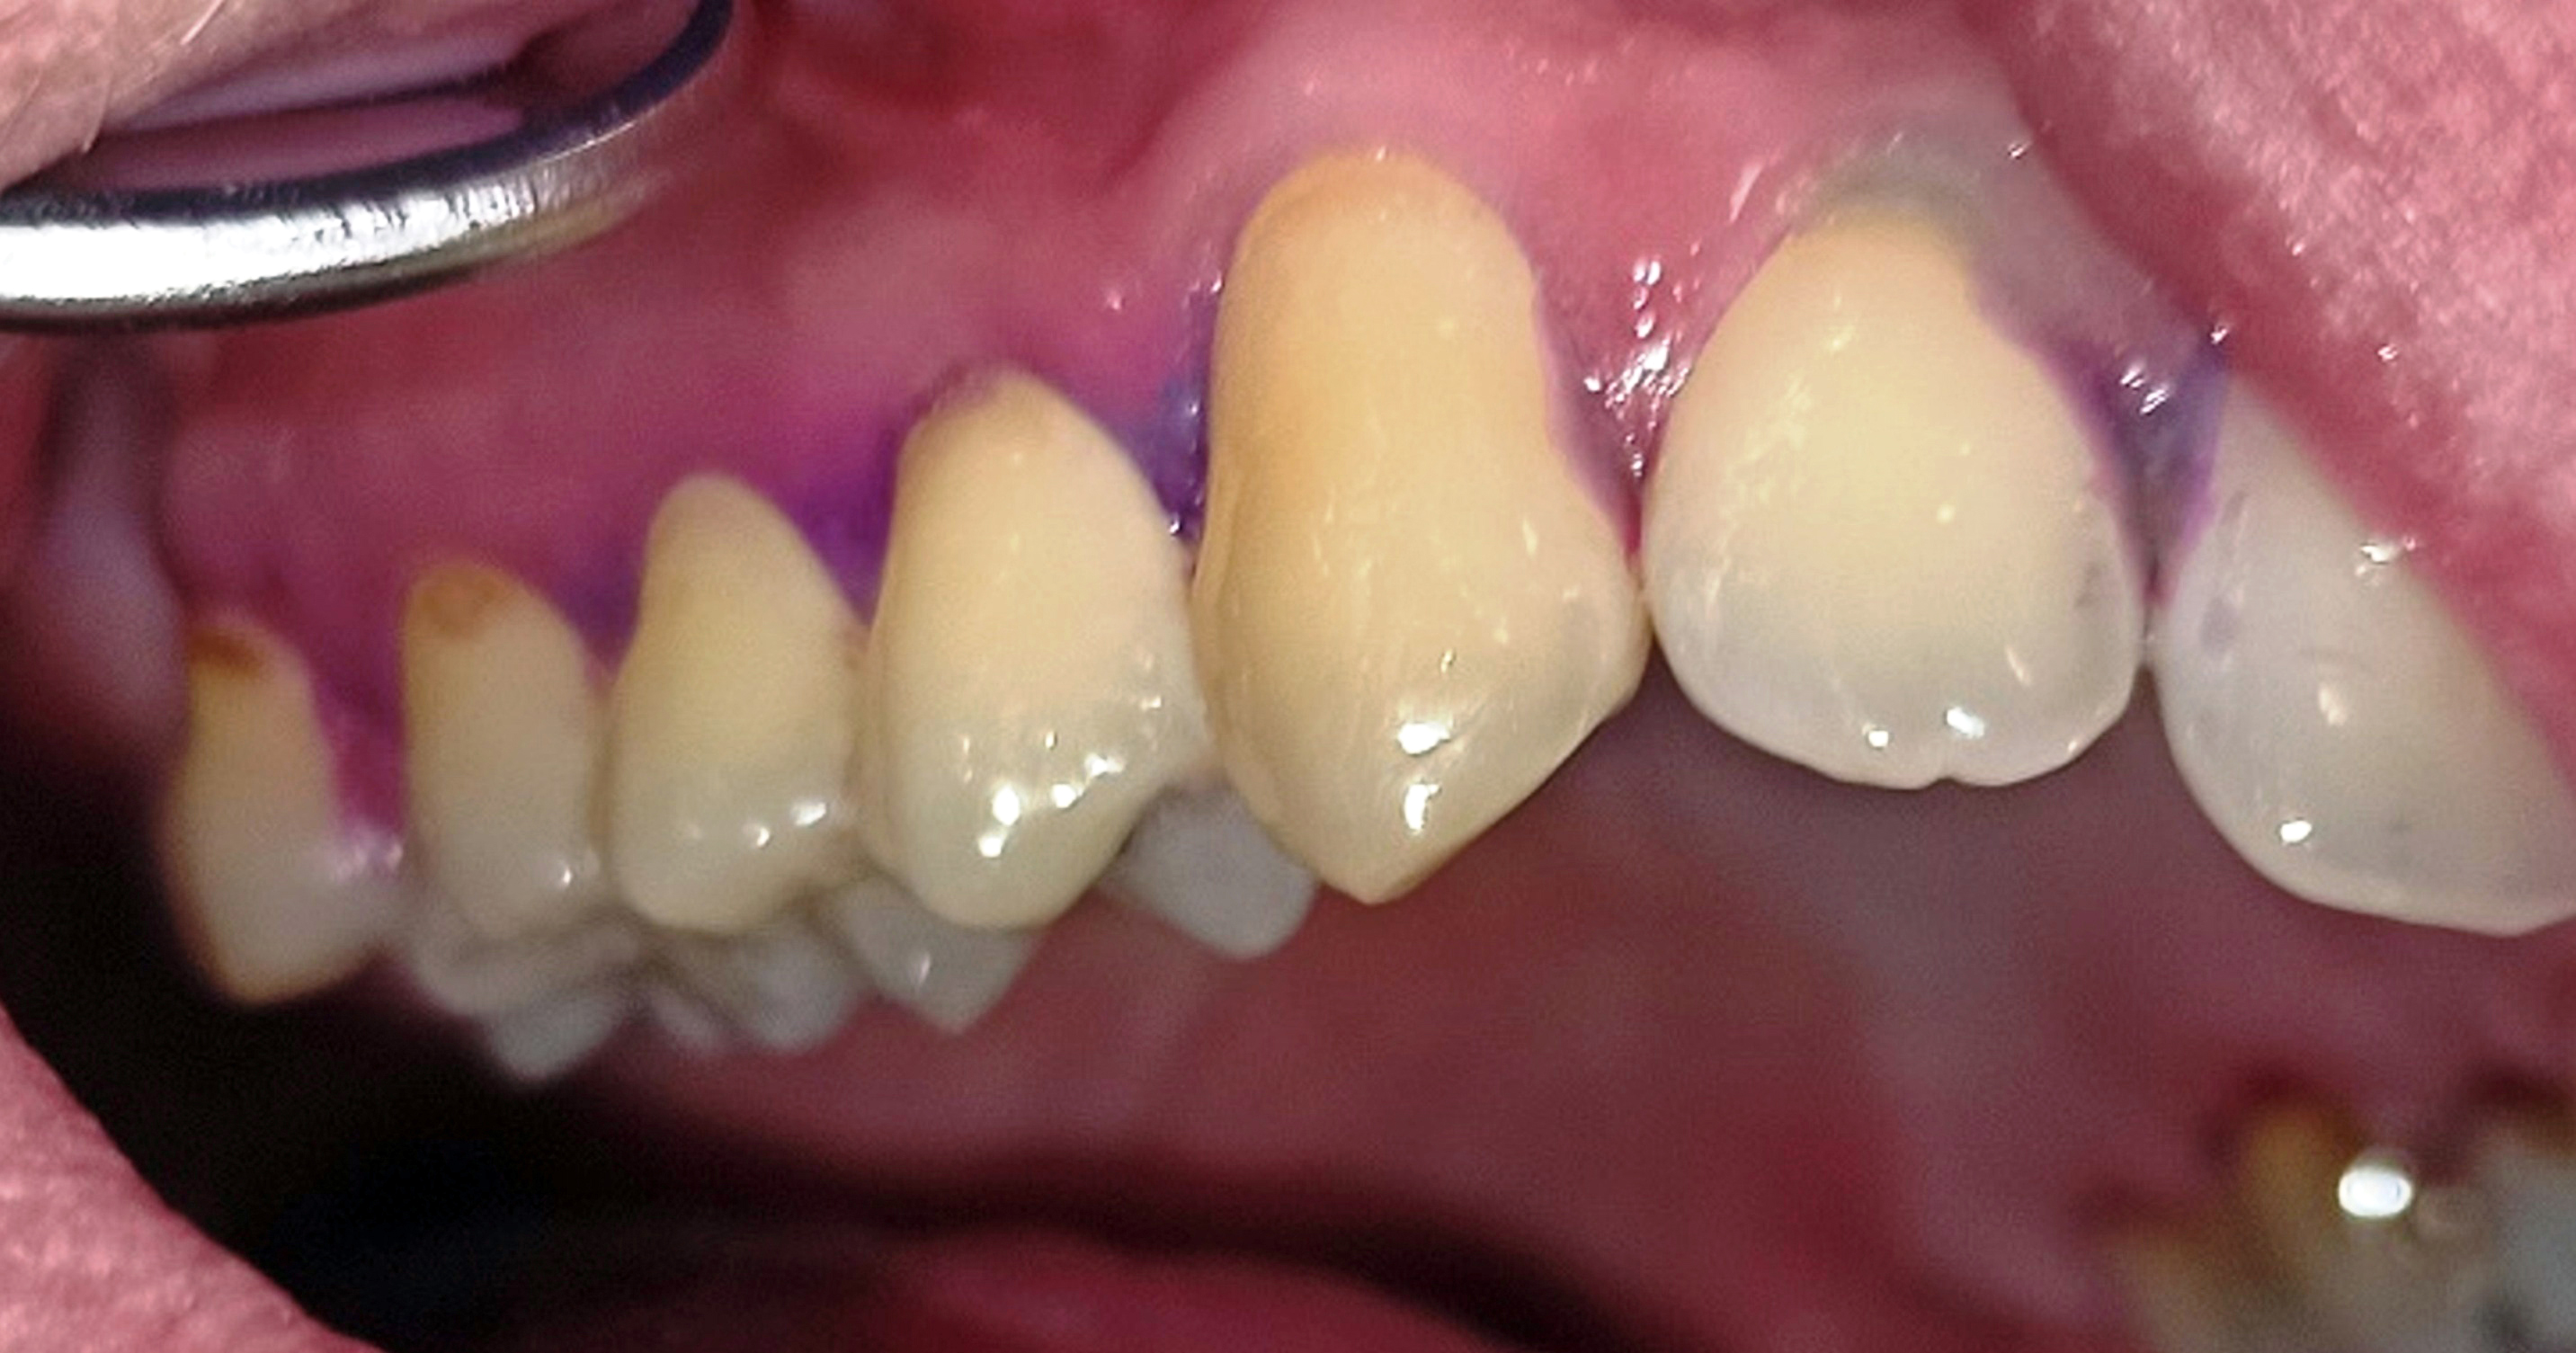

Innerhalb der Gruppe der Patienten mit Fazialisparese wurde außerdem ein Vergleich der Mundgesundheit zwischen beiden Mundhälften durchgeführt. Dabei wies die paretische Seite eine signifikant höhere Plaque-Kontamination, mehr Blutungen und höhere PSI-Werte auf als die nicht paretische Seite (Tab. 3). Die Plaque-Kontamination war in Bezug auf den API auf der paretischen Seite um 10,9 % (p = 0,004) höher als auf der nicht paretischen Seite. Ebenso wiesen die vestibulären Zahnoberflächen der paretischen Seite mehr Biofilm auf als die der nicht paretischen Seite (p = 0,002; s. Tab. 3, Abb. 2a und b). Dabei war der Unterschied bei den männlichen Patienten (0,8 vs. 0,5; p = 0,001) größer als bei den weiblichen Patienten (0,6 vs. 0,4; p = 0,002). Außerdem wurde bei Patienten mit rechtsseitiger Fazialisparese ein größerer Seitenunterschied (0,7 vs. 0,5; p < 0,001) dokumentiert als bei Patienten mit linksseitiger Fazialisparese (0,5 vs. 0,4; p = 0,043). Ursächlich erschien die Händigkeit der Patienten. Während bei Patienten mit linksseitiger Fazialisparese die Erkrankung auf der für Rechtshänder besser zu reinigenden Mundhälfte vorlag, waren rechtshändige Patienten mit rechtsseitiger Fazialisparese einer doppelten Belastung ausgesetzt (18). Die Gingivablutung nach Sondierung war auf der paretischen Seite ebenfalls signifikant höher als auf der nicht paretischen Seite (s. Tab. 3). Das spiegelte sich sowohl bei den Werten des SBI (s. Tab. 3, Abb. 3) als auch bei den Werten des PBI (s. Tab. 3, Abb. 4a und b) wider. Die Sondierungstiefen waren auf der paretischen Seite im Vergleich zur nicht paretischen Seite tiefer und der Attachmentverlust war höher. Dabei konnte jedoch kein signifikanter Unterschied nachgewiesen werden. Der mittlere PSI erreichte auf der paretischen Seite signifikant höhere Werte als auf der nicht paretischen Seite (p = 0,032; s. Tab. 3), was auf eine schlechtere Gingivagesundheit hinweist. Darüber hinaus war die Prävalenz unbehandelter kariöser Läsionen auf der paretischen Seite höher als auf der nicht paretischen Seite (s. Tab. 3). Ein Fallbeispiel illustriert eindrucksvoll die Unterschiede zwischen der kariesfreien nicht paretischen Seite und der paretischen Seite mit multiplen aktiv kariösen Läsionen (Abb. 5a und b). Zusätzlich wies die paretische Seite eine höhere Anzahl an Restaurationen auf als die nicht paretische Seite (s. Tab. 3). Hinsichtlich des Zahnsteinbefalls wurden auch im Seitenvergleich der Mundhälften keine signifikanten Unterschiede zwischen den paretischen und den nicht paretischen Seiten festgestellt. Im Einzelfall wurden jedoch eindrucksvolle Unterschiede zwischen den Mundhälften deutlich (Abb. 6a und b).